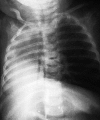

Pulmonary agenesis (PA) is a rare congenital anomaly, which may be unilateral or bilateral. Unilateral PA may be associated with nonspecific respiratory symptoms. We report the case of 5-month-old infant who presented a normal development until the age of 4 months when a respiratory infection caused an acute respiratory distress syndrome with a fatal outcome. The autopsy findings depicted the right lung agenesis without any other concomitant malformation. Although respiratory symptoms represent frequent complaints in pediatrics, the aim of this study is not only to draw attention to the unilateral pulmonary agenesis as a possible underlying malformation in children who present recurrent and severe respiratory symptoms, but also to report a case diagnosed at autopsy.